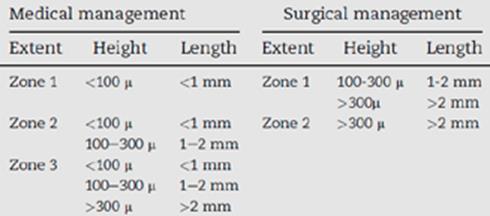

Η ταξινόμηση του Mackool διακρίνει τις ΑΔΜ σε “planar” και “nonplanar” ανάλογα με το εάν η απόσταση μεταξύ της αποκολλημένης μεμβράνης και του στρώματος είναι μικρότερη ή μεγαλύτερη του 1mm, αντίστοιχα4. Βάσει αυτού του χαρακτηριστικού και της θέσης της αποκόλλησης (κεντρική ή περιφερική) προκύπτει η πρόγνωση και καθορίζεται η θεραπευτική προσέγγιση. Αντίστοιχα, η ταξινόμηση κατά Jain5 ή ο αλγόριθμος HELP6 (Πίνακας 1) περιγράφουν την πρόγνωση και προτείνουν θεραπευτική στρατηγική με βάση τα ανατομικά χαρακτηριστικά και τη θέση της αποκόλλησης.

Η θεραπευτική αντιμετώπιση των ΑΔΜ εξαρτάται από τη θέση, την έκταση, την απόσταση από το στρώμα και την ύπαρξη ή όχι αναδιπλούμενων άκρων. Το κρίσιμο στοιχείο είναι να παρθεί έγκαιρα η απόφαση, με βάση την κλινική εικόνα και τον χρόνο που έχει περάσει από το χειρουργείο, για συντηρητική ή χειρουργική προσέγγιση, ώστε να επιτευχθεί το βέλτιστο οπτικό αποτέλεσμα7. Η συντηρητική θεραπεία περιλαμβάνει την τοπική χορήγηση κορτικοστεροειδών και υπέρτονων κολλυρίων ή αλοιφών. Τα κορτικοστεροειδή περιορίζουν τη φλεγμονή και επιβραδύνουν την ίνωση, ενώ τα υπέρτονα διαλύματα μειώνουν το κερατοειδικό οίδημα. Η δράση τους είναι παροδική και απαιτείται η σταδιακή αυτόματη επανασύνδεση της μεμβράνης για να επανέλθει ο κερατοειδής στην προτέρα κατάσταση. Εάν αυτό δεν συμβεί εντός τεσσάρων εβδομάδων, ενδείκνυται χειρουργική παρέμβαση.